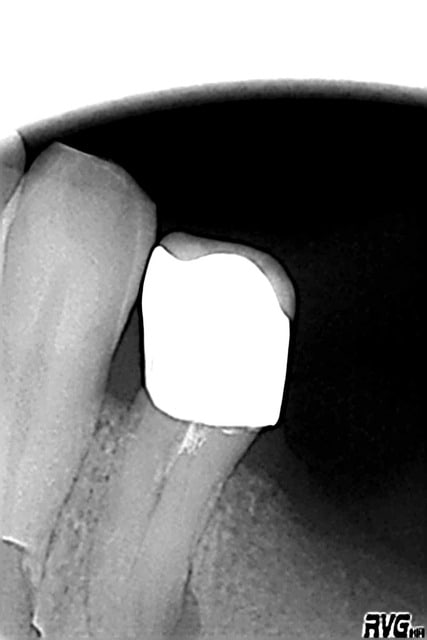

Bon désolé, je ne crois pas qu'il y ai un SC33 dans ce truc, à moins que ... Ceci dit j'aimerais autant pas, je pourrais reprendre l'endo à travers la Cr, même si Au moins 2 canaux ... (je suis bien con)

R2 p8tzop - Eugenol

Capture d  cran 2015 03 12 12.28 - Eugenol

chicot29

26/04/2016 à 19h28

Bon là il y en avait un. -)

Capture d e cran 2016 04 26 17.24 - Eugenol